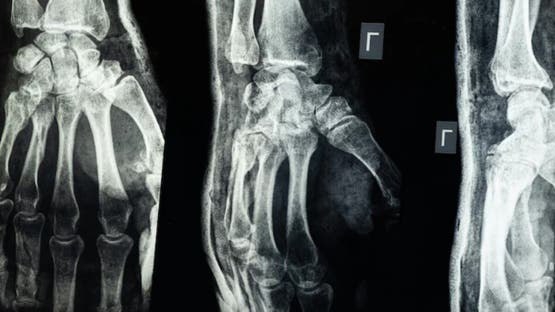

أعلن فريق بحثي في مقاطعة تشيجيانغ شرق الصين عن ابتكار طبي جديد يتمثل في "غراء عظمي" قادر على معالجة الكسور وتركيب الشظايا العظمية خلال ثلاث دقائق فقط، في خطوة وُصفت بأنها اختراق علمي في عالم جراحة العظام، بحسب ما نقل موقع "إن دي تي في" NDTV.

وأكدت الاختبارات المعملية أن Bone-02 نجح في تحقيق نتائج جيدة من حيث السلامة والفعالية. وفي إحدى التجارب، أُجريت العملية في أقل من 180 ثانية (ثلاث دقائق)، بينما كانت طرق العلاج التقليدية تتطلب وقتاً طويلاً لزرع صفائح فولاذية ومسامير.

وبحسب الاختبارات المعملية، تمكن الغراء من تحقيق قوة ربط تفوق 400 رطل، وقوة قص تبلغ نحو 0.5 ميغاباسكال، وقوة ضغط تقارب 10 ميغاباسكال. كما أظهرت التجارب على أكثر من 150 مريضاً نتائج ناجحة، ما يعزز احتمالية أن يصبح بديلاً للزراعات المعدنية التقليدية التي تُستخدم في تثبيت العظام. كما يقول العلماء إنه قد يقلل أيضًا من مخاطر العدوى.